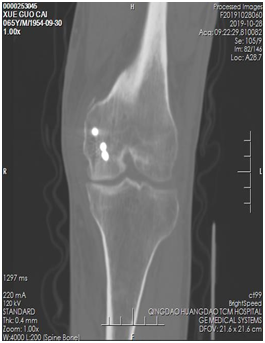

薛大叔左膝外侧有(以腓骨小头为中心)约10cmX15cm皮肤挫伤,其中间约5cmX8cm皮肤色紫,血运差;膝关节内上侧有约6cmX25cm皮肤挫伤,血运不满意 。医生为其进行了详细检查,确诊为左股骨内后髁骨折(Hoffa骨折)、左腓骨小头骨折、左膝内侧半月板损伤、左下肢挫裂伤 。

术前CT片